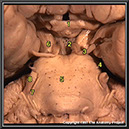

N1A6P4

24